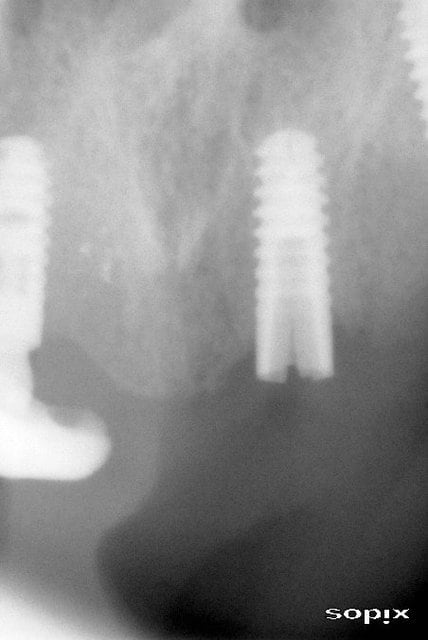

Je ne fais pas d'implanto, mais au regard de la Rx, mon vieil instinct de matou me dit que c'est trop fin, que la couronne est trop haute, que l'etraglement est trop important.

Y'avait l'air d'avoir de la place, non? pourquoi dans ce cas ne pas prendre des dimensions qui ressembloent a celles d'une racine de premo???

oui, mais le problème n'est pas dans le sens mésio distal...plus certainement en vestibulo palatin...

m'est d'avis qu'un petite expansion aurait permis de placer un 3.75 au lieu d'un 3.3...mais çà n'enlève pas le problème de growly qui a eu le même problème sur cet implant standard de 3.75...

Parce que des fois en VD on n'a pas la place, j'aurais pu faire de l'expansion c'est sûr, j'aime bien en plus mais c'était une extrac imp immédiate, pas osé.

Je pense quand même qu'en alliage de titane ça n'aurait pas cassé, reste à savoir si le design de l'implant, et les microspires ne fragilisent pas trop.

Un autre design dans ce diamètre, et an alliage n'aurait pas cassé je pense.